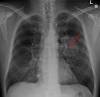

Lung Cancer Awareness Month – How To Get Involved Now! Nov 16, 2020 3:56 pm ET. Reply. November is Lung Cancer Awareness Month, a time to share important information and highlight stories of patients, survivors, and their families to raise awareness of this important cause.This year, more than 228,000 people ...

Study identifies patients with lung cancer most likely to respond to immunotherapy Scientists are beginning to unravel one of the biggest challenges with immunotherapy: why some people with cancer respond to the treatment, while others may not respond at all. In a new study, researchers at the UCLA Jonsson Comprehensive Cancer ...